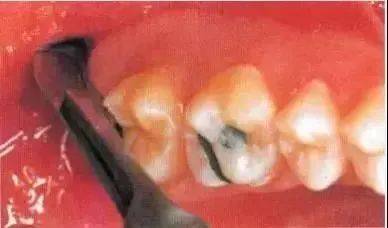

部分远中阻生的左下颌第三磨牙的拔除步骤:

1.以阻生牙远中的釉骨质文界处为参照估计其最大埋伏深度;

2.用装在机头上的圆钻解除远中骨阻力,显露出阻生牙的(牙合)面,然后用同样的圆钻解除牙冠最大周径以上的横向骨阻力;

3.使用纺锤形的车针朝向埋伏最深的区域(远中面的颈部)切割牙冠;

4.用合适的牙挺能顺利地挺裂牙冠井挺出牙片;

5.用装在反角机头上的纺锤形的车针分根;

6.先取出近中根,然后往远中方向取出远中根

全颌曲面断层×线片。切割牙冠时应经过阻生牙远中面的牙颈部的釉牙骨质交界处。

下颌升支前缘的骨吸收区有利于牙片的取出。

去除颊侧部分骨阻力后,用装在反角机头上的纺锤形车针切割牙冠。用柔韧的小拉钩保护舌侧的黏骨膜(及舌神经)。

该病例也可以不切割牙冠而拔除。拔牙时,去除了牙根间隔。